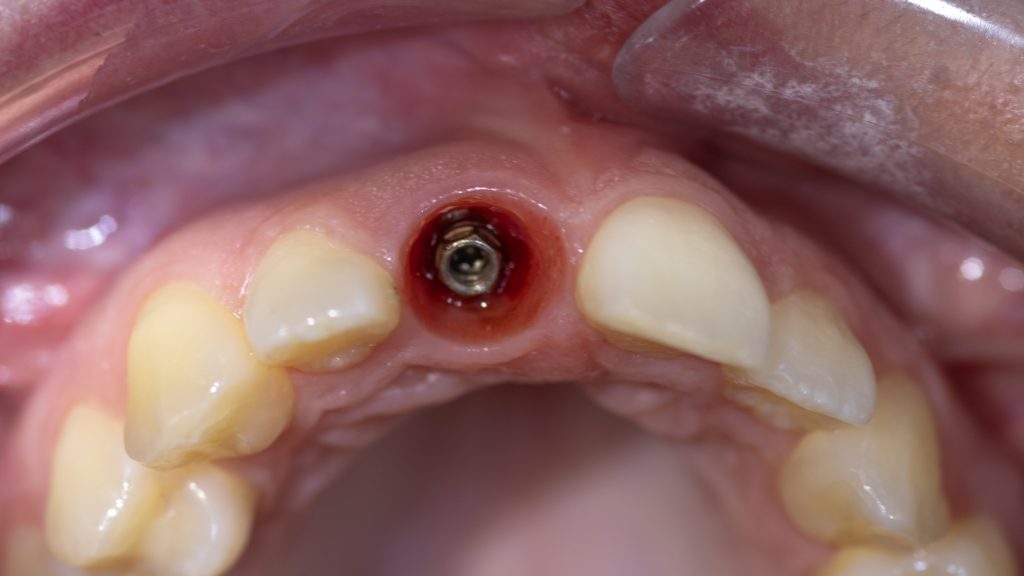

after initial healing